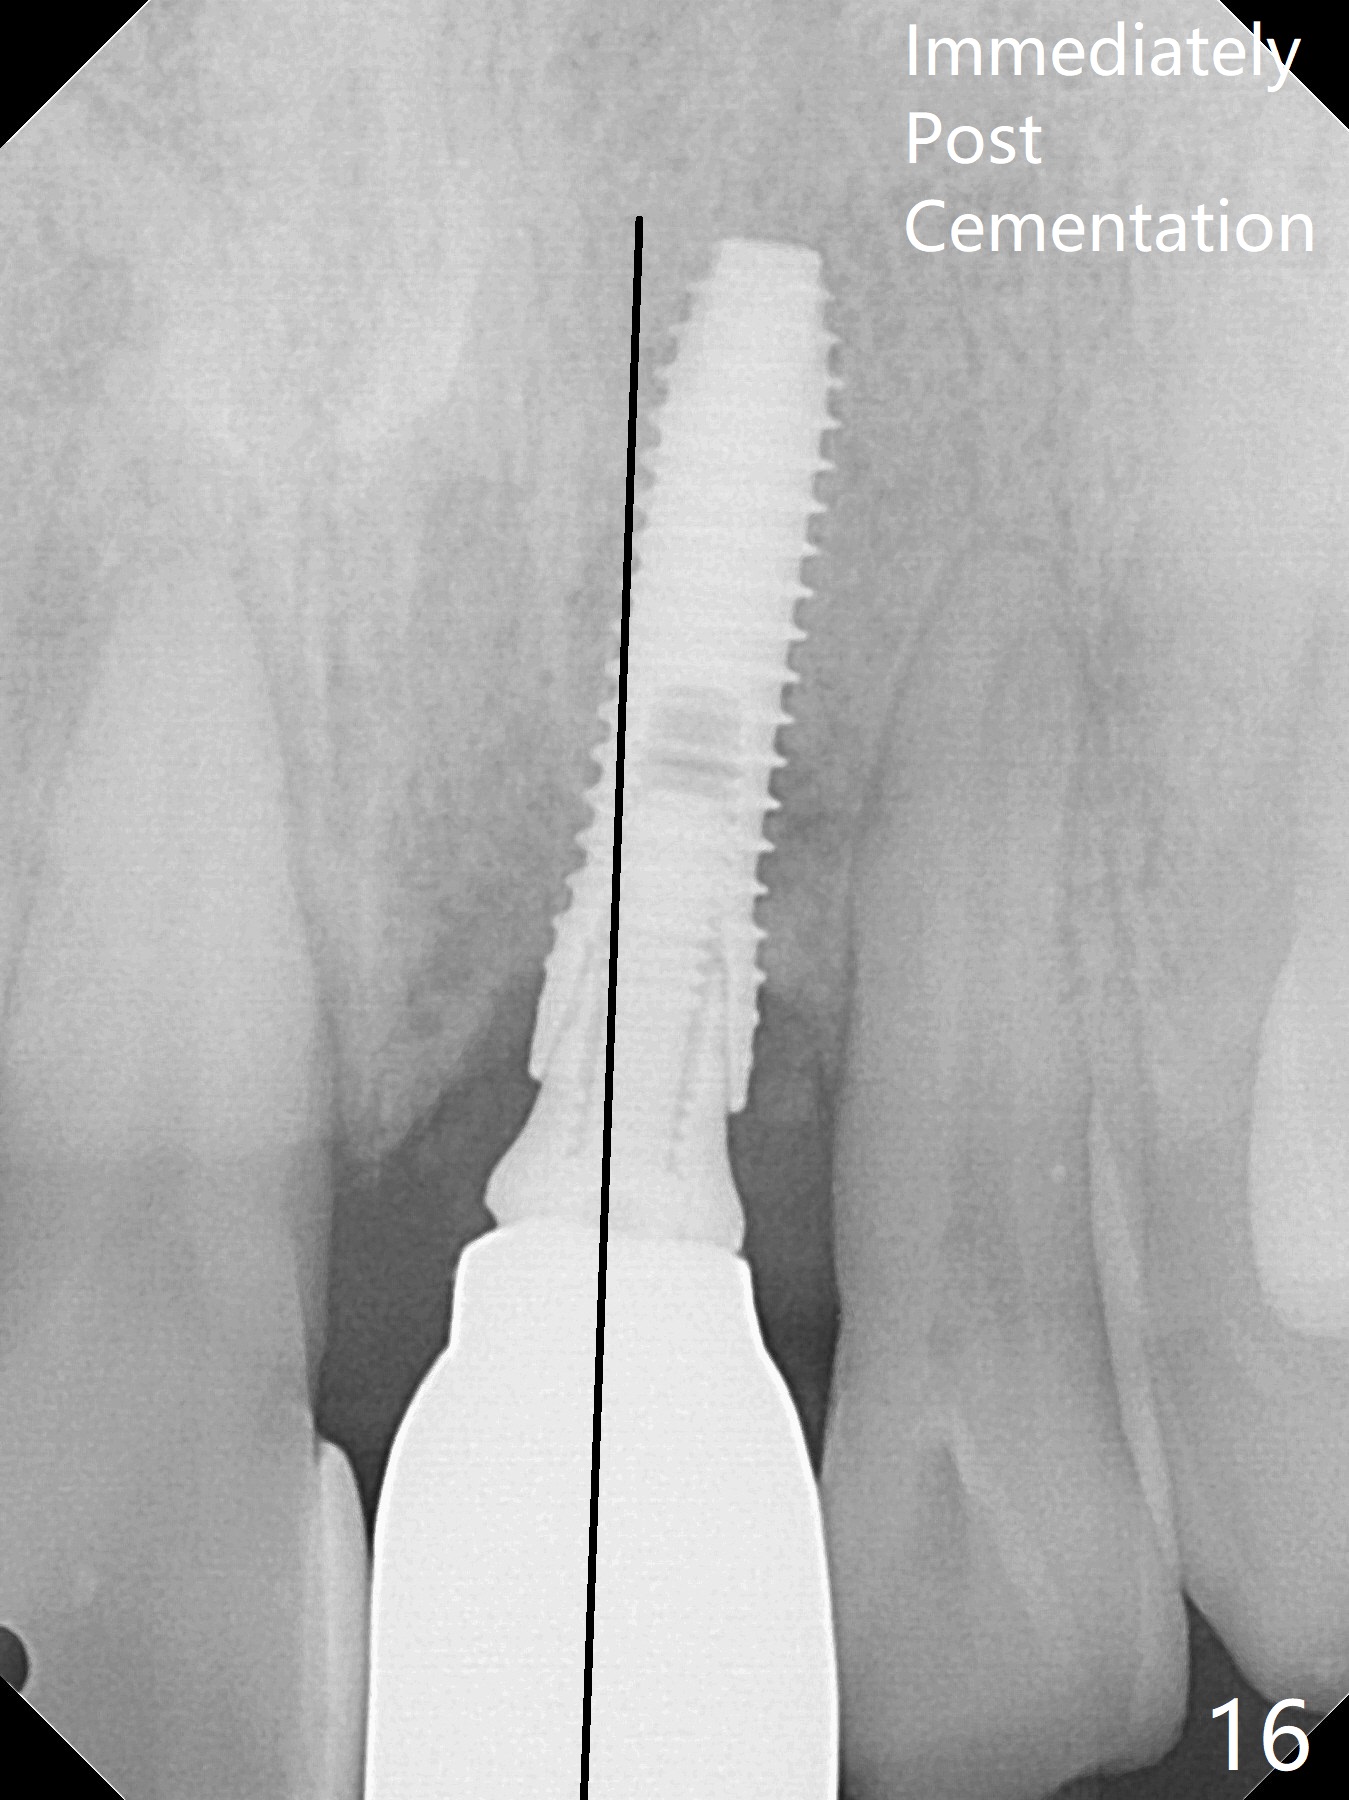

Nearly 7 months postop, the immediate provisional at UL1 is removed; with the mesial reduction of UL2 from 7 to 6 mm (Fig.1), an angled abutment is to be changed (4.5x15 degree, 2 mm cuff). A new provisional (Fig.2,3) co-incides with the facial midline. Brackets will be placed between UR4 to UL3 except UL2 (symptomatic once with chronic periodontitis) with initial proximal reduction between UR1-4 in preparation to correct cross bite of UR2. Twelve days later, the patient returns for UR5-UL3 bracketing after UR1-4 initial proximal reduction with 14 niti wire (Fig.4-6). UR1 moves mesial 20 days post open coil spring (Fig.7 arrow), while UL1 debracketes after permanent re-cementation of the temporary crown last visit (*, no re-bracketing, since it appears not essential). Before placement of 20 ss wire, diastemata are created by proximal reduction (Fig.8 *). In fact UR1 moves mesial, while UR3 does not move distal with the open coil. With placement of UR6 (implant) molar band, UR3 is distalized effectively. With sling shot, UR2 is almost labialized in one appointment (Fig.9). After consolidation of the diastemata between UR1-6 with power chains following UR2 cross bite correction (Fig.10), the restoration space for UL1 seems to be too large (Fig.11). Next visit, check the midlines, take 1-2 PAs for #7-9 and determine whether a straight abutment should be changed back and whether composite should be placed UR1 mesial to reduce the space. One week later, composite is added to the mesial surface of the tooth #8 to increase its width, while the provisional at #9 is relined to improve the interdental papilla (Fig.12). Minimal bone loss at UR2 is observed 8 months post banding (Fig.13), while the socket at UL1 seems to have healed except the most coronal 1 year 3 months postop (Fig.14 *). The margin of the abutment should be uneven, more coronal proximal than buccopalatal (Fig.15). The final crown has an open margin, partially due to less ideal trajectory (Fig.16 (black line: ideal trajectory, nearly 1 year 4 months postop)). Guided surgery could solve the problem. Sticky bone may restore the buccal plate defect. Die shows that the implant is palatally placed (Fig.17). CT will be taken to determine whether the implant perforates the palatal plate.